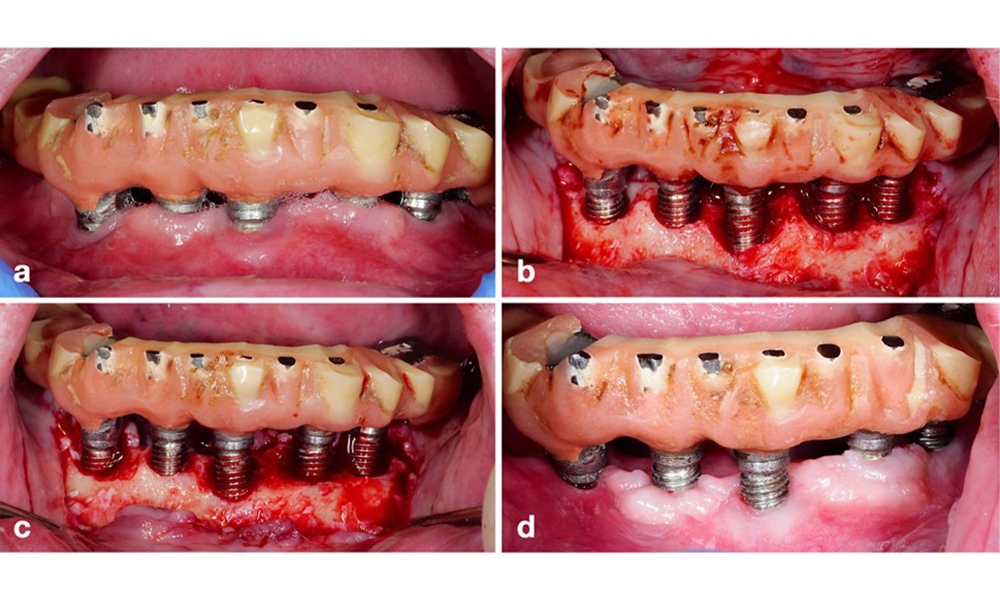

Die prothetische Restauration sollte bei einer nicht-chirurgischen ebenso wie bei einer chirurgischen Behandlung abgenommen werden, um einen besseren Zugang zur Implantatoberfläche zu ermöglichen. Die Wahl der chirurgischen Intervention (z. B. resektiv, rekonstruktiv oder eine Kombination) hängt von mehreren Faktoren ab: (1) Morphologie des Defekts (z. B. horizontal, Dehiszenz, intraossär oder eine Kombination) (Abb. 10), (2) Implantatoberfläche (also gedreht oder modifiziert/„rau“) und (3) Vorhandensein oder Fehlen einer ausreichend keratinierten und anhaftenden Schleimhaut.

Bei hauptsächlich horizontalen Knochenverlusten oder breiten Defekten mit begrenztem Knochenregenerationspotenzial sollte auf ein resektives Verfahren (also Gingivektomie und/oder apikal positionierter Lappen mit/ohne Knochenrekonturierung) zurückgegriffen werden (Abb. 11).